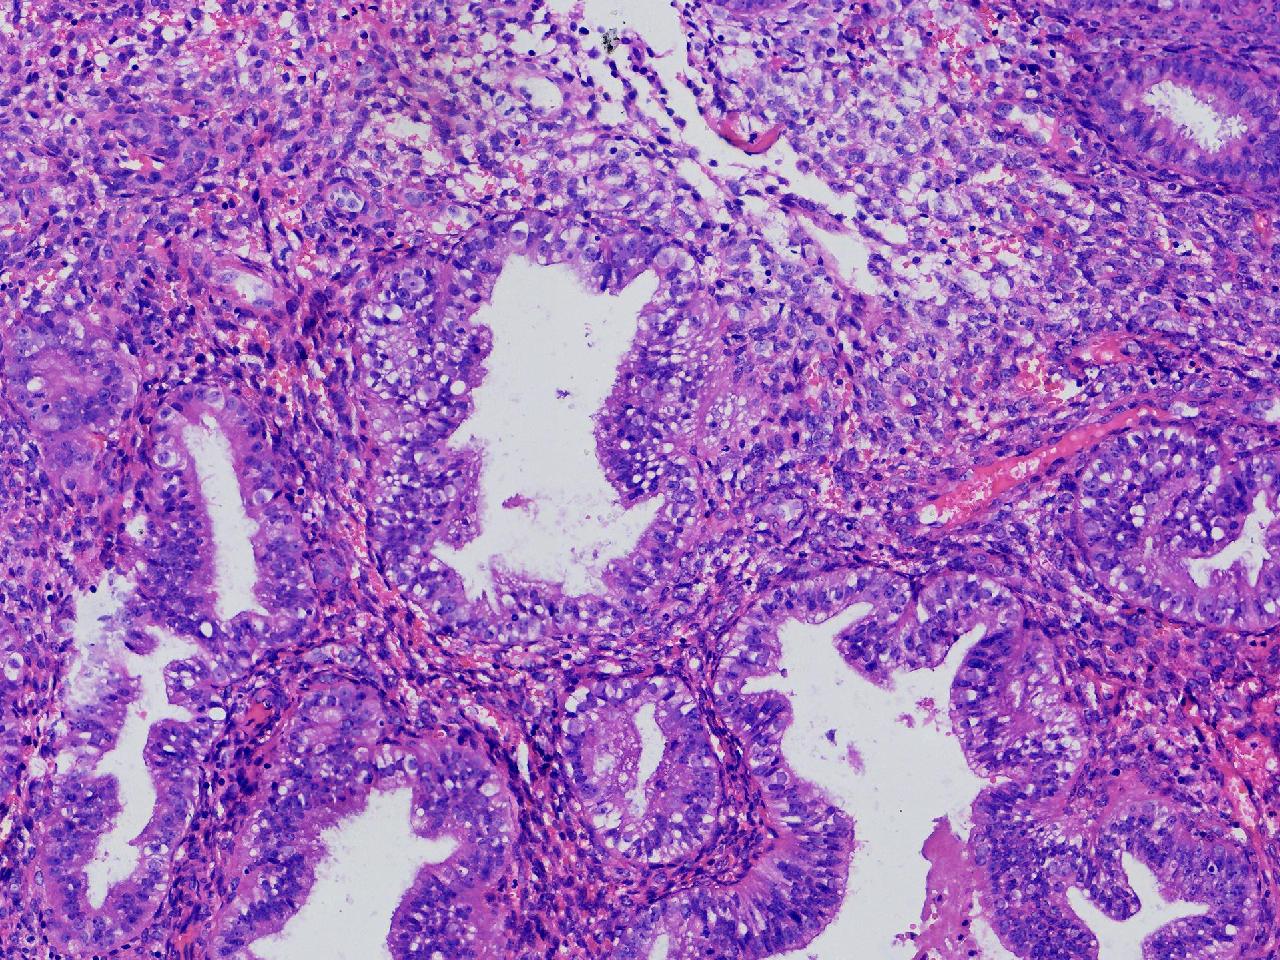

请教诊断.有没有非典?

性别

女

年龄

50岁

女,50岁,彩超示:内膜厚1.3cm。

子宫内膜

灰粉色不整形软组织多块,2X2X1厘米。

无非典型性子宫内膜增生

无非典。